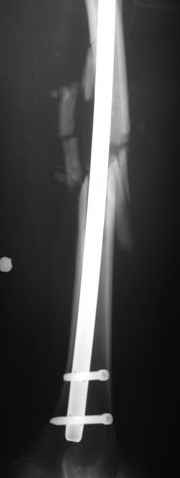

В приложении пример огнестрельного ранения бедра, оперированного на 2 сутки после ранения.

Штифтование было выполнено только на вторые сутки по причине задержки перевода из другого госпиталя, АБ профилактика была начата в другом учреждении, с момента госпитализации пациента к ним. Входное пулевое отверстие и зона введения штифта зажили первичным натяжением.

В конце 90-ых попалось несколько статей по nail exchange procedures in treatment of posttraumatic osteitis и решился попробовать на огнестрельных переломах, которые до этого лечил по полной схеме:расширенный дебрайдмент+ внешняя фиксации+промывные системы с антибиотиками и без антибиотиков в промывной среде. Всё заканчивалось длительной госпитализацией, плохими функциональными результатами( страдала функция колена), необходимостью повторной хирургией - отсроченная внутренняя фиксация переломов, длительной реабилитацией. На гвоздях процесс пошел лучше: остеомиэлитов не было и больные мобилизовывались быстрее.

Единственно что наблюдал - замедленная консолидация, судя по серийным Рг граммам. В приведенном случае прии вялом мозолееобразовании сделал ошибку, решившись динамизировать гвоздь - перелом сросся со значительным укорочением бедра - повторная хирургия по удлинению бедра и проксимальным запиранием, больной мобилизован и вполне доволен(кстати заметить больной с ВИЧ инфекцией - изначально скомпрометированный иммунитет и несмотря на это, всё прошло без костной и мягкотканной инфекции.